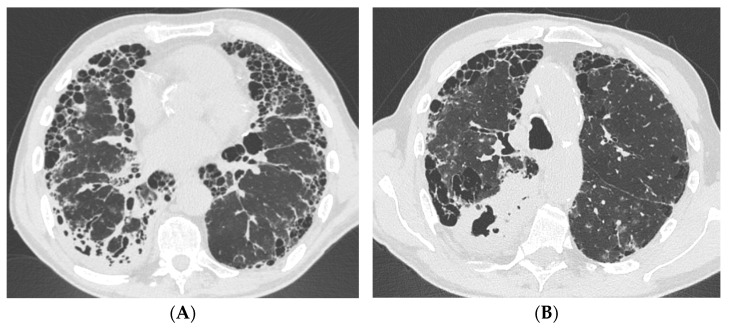

Background: Interstitial lung diseases (ILDs) are a heterogeneous group of conditions that can cause fibrosis of the lung interstitium, resulting in respiratory failure and death. Patients with an ILD, particularly idiopathic pulmonary fibrosis (IPF) or connective tissue disease-associated ILDs (CTD-ILDs), are prone to develop chronic pulmonary infections such as tuberculosis (TB) and non-tuberculous mycobacterial pulmonary disease (NTM-PD).

Methods: This case series examines the management of three ILD patients with a usual interstitial pneumonia (UIP) pattern and concomitant NTM-PD or TB at National Institute for Infectious Diseases "Lazzaro Spallanzani" in Rome, Italy, over three years (2019-2022).

Results and conclusions: Multi-disciplinary discussion (MDD) was crucial to define the therapeutic approach due to the increased risk of side effects and drug interactions. Our work underscored how a comprehensive diagnostic evaluation, enriched by MDD, is useful for optimizing the management and reducing drug-related adverse effects and interactions in ILD patients with cavitary lesions.